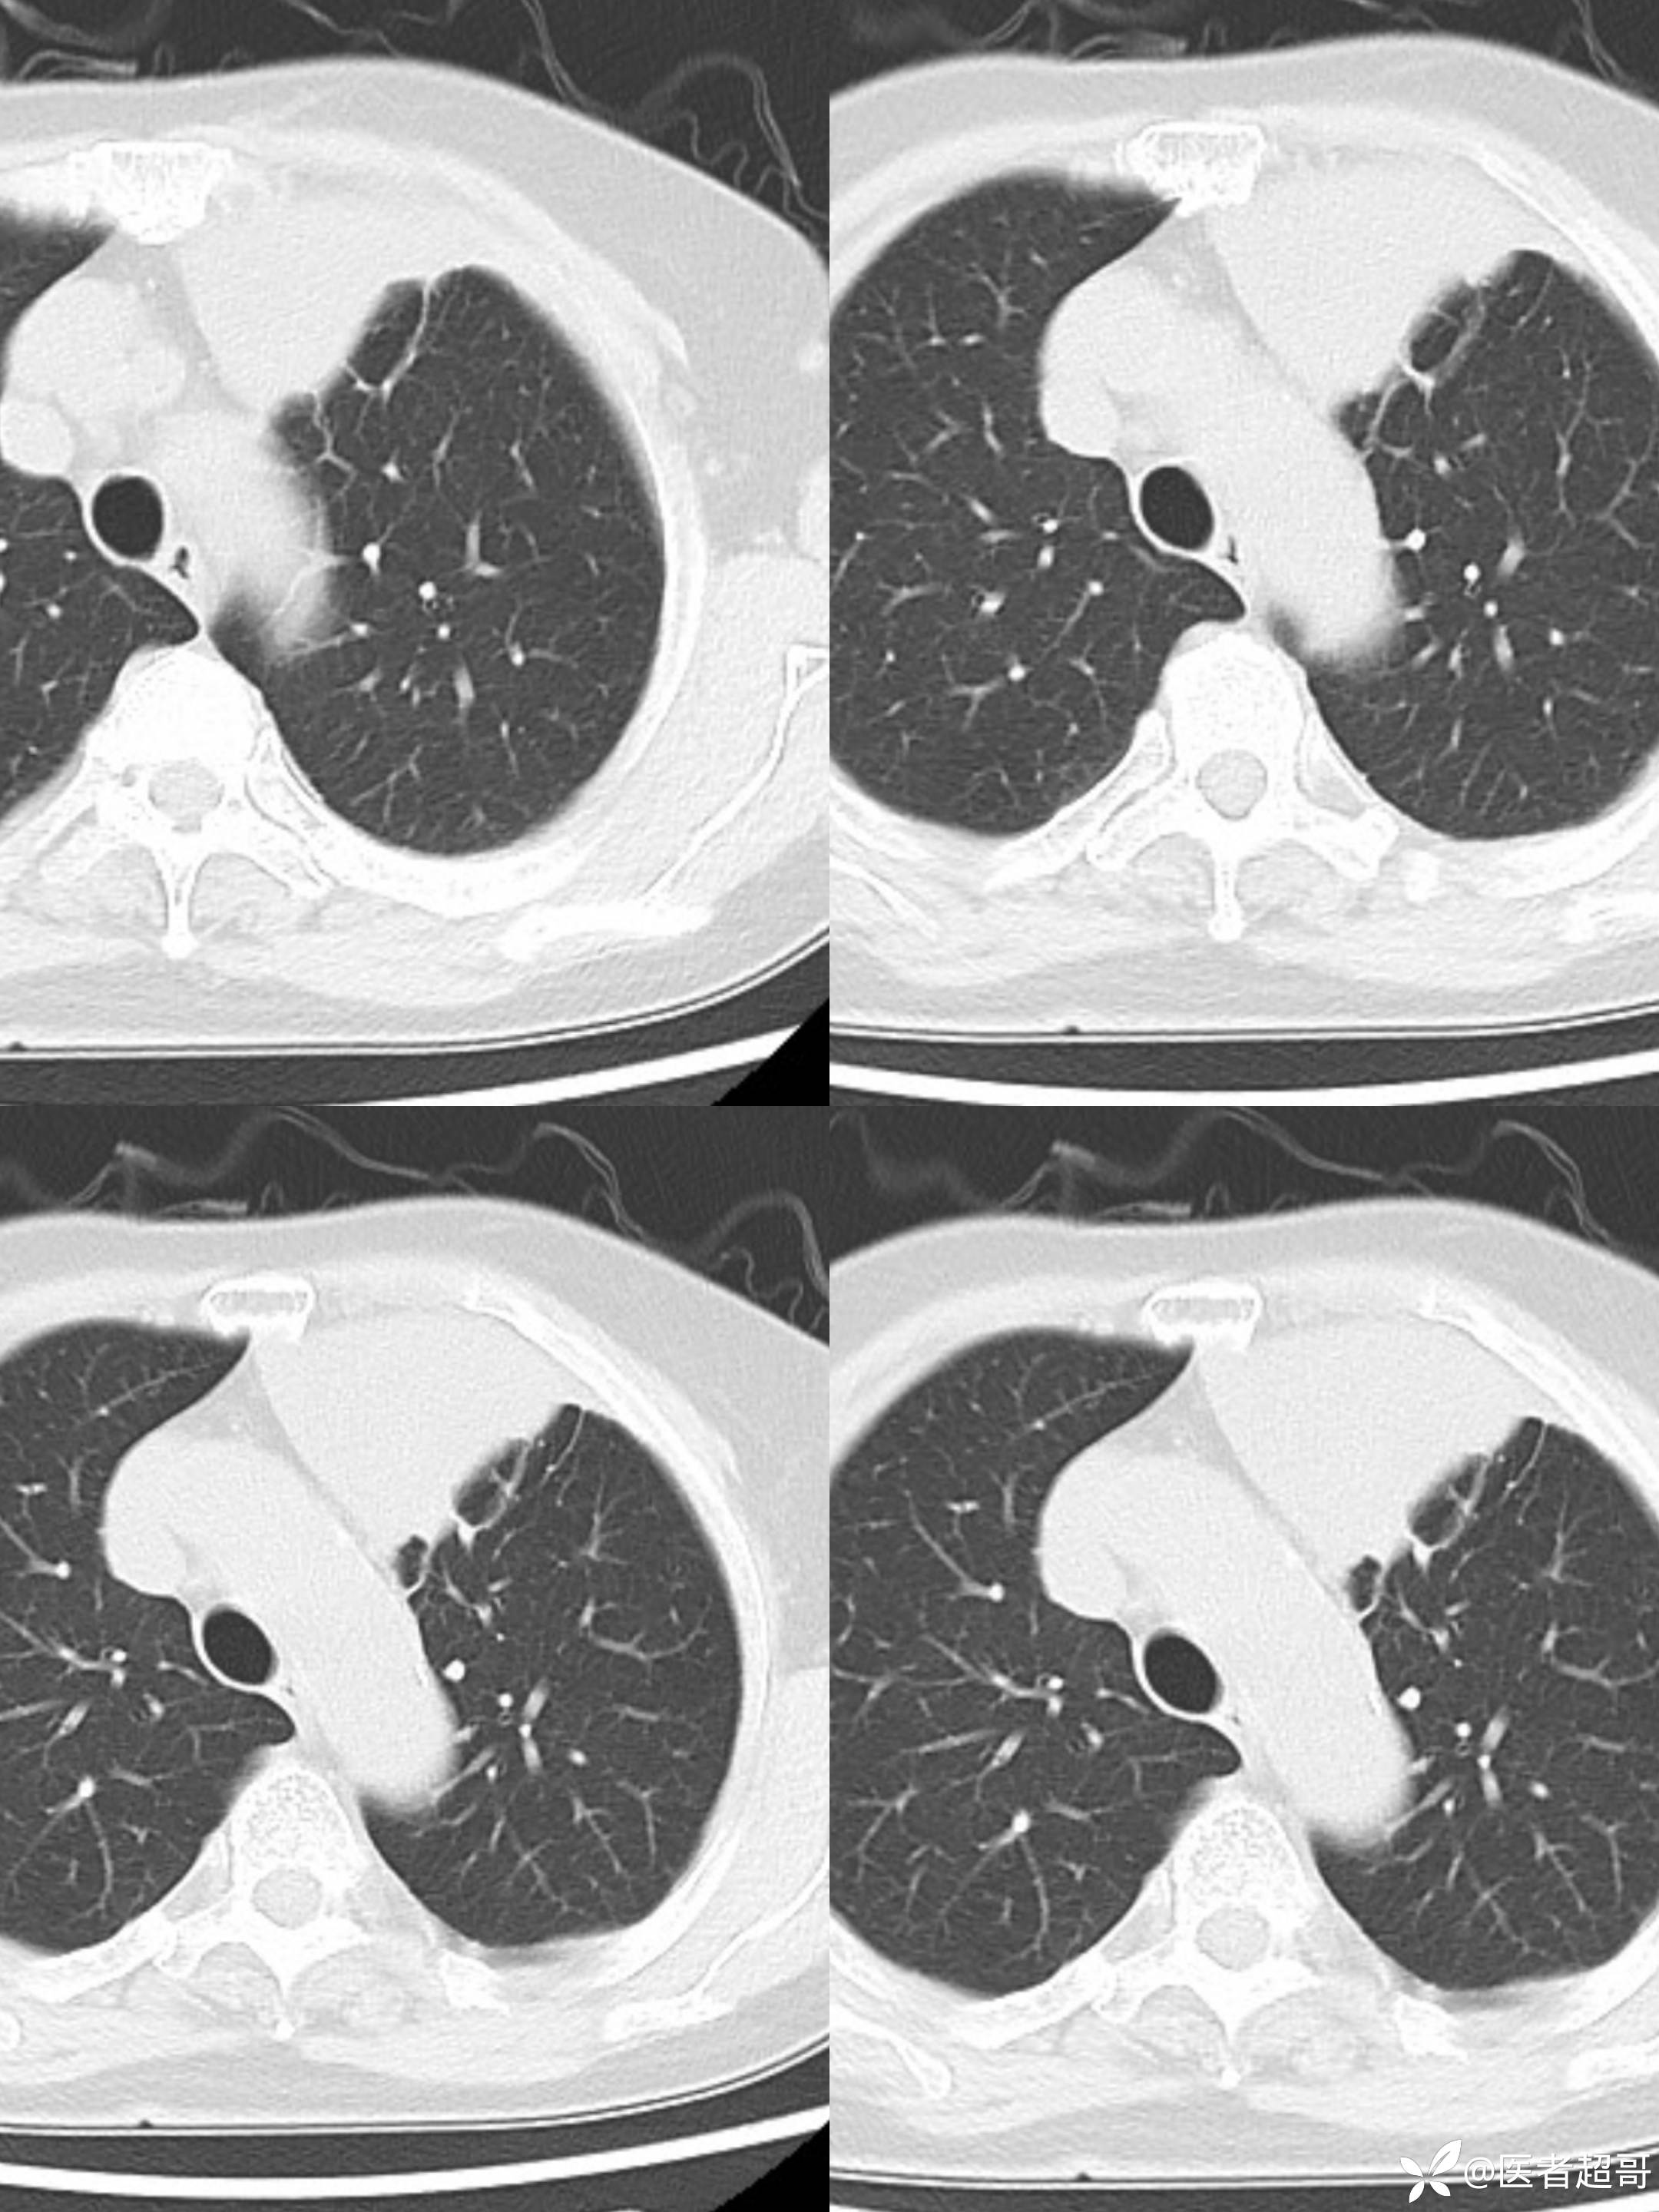

女73岁,体检发现左上纵隔占位1周

患者于1周前体检行CT检查提示:“左上纵隔见不规则团块状软组织密度影,大小约90*63mm”,患者平素偶有头晕,无明显胸闷气急,今为进一步治疗来我院就诊, 门诊以"左上纵隔肿物"收入院。